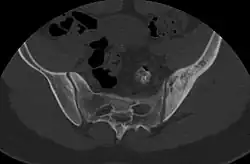

- ^ Nguyen, Nghi; Khan, Mujahid; Shah, Muhammad (2017). "Primary B-cell lymphoma of the pelvic bone in a young patient: Imaging features of a rare case". Cancer Research Frontiers. 3 (1): 51–55. doi:10.17980/2017.51. ISSN 2328-5249.